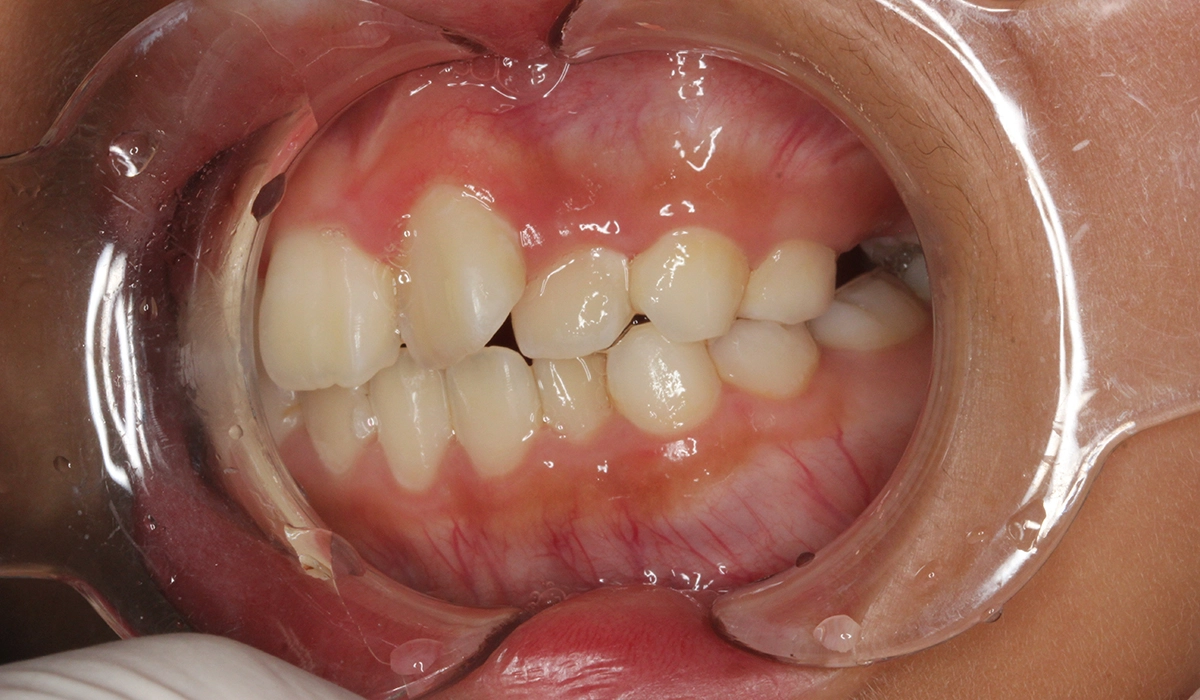

術前:右側